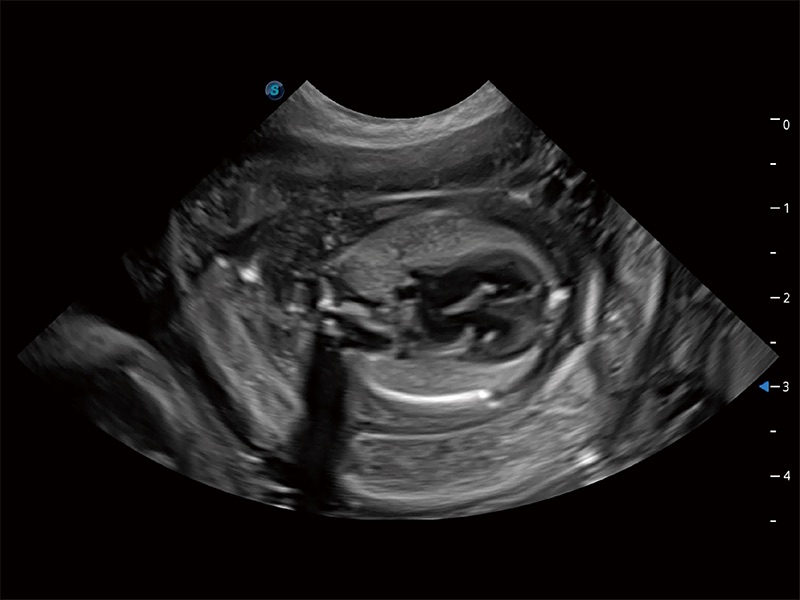

動物是人類最親密的朋友和最值得信賴的伙伴。開立醫(yī)療也一直致力于探索動物專用的超聲影像解決方案。全新推出的ProPet系列,是開立在動物超聲影像智能化、專業(yè)化、精準(zhǔn)化的一次跨越式革新。動物不能用言語來表述自己的不適,通過超聲影像,ProPet系列搭建了動物醫(yī)生與不同物種溝通的“橋梁”,為動物醫(yī)生注入了“治愈之力”。 ProPet 80 是開立醫(yī)療匠心打造的一款高端動物專用彩超,采用性能卓越的全新硬件架構(gòu),極大提升超聲系統(tǒng)的運(yùn)行效率和數(shù)據(jù)處理能力,幫助動物醫(yī)生從容應(yīng)對日益增多的挑戰(zhàn)性病例和日益多樣化的臨床需求。

高性能和先進(jìn)的臨床應(yīng)用工具可以為動物醫(yī)生提供臨床信心。ProPet 80 搭載了先進(jìn)的腹部和淺表應(yīng)用工具,幫助醫(yī)生在日常臨床實踐中發(fā)揮前所未有的作用。

ProPet 80 全新的動物超聲智能軟件和豐富的探頭群,為動物醫(yī)生提供了高清晰度和精細(xì)分辨率的圖像,無論在寵物、馬科、畜牧還是實驗室動物等應(yīng)用中都可以輕松應(yīng)對,為您的日常工作帶來滿意的體驗。